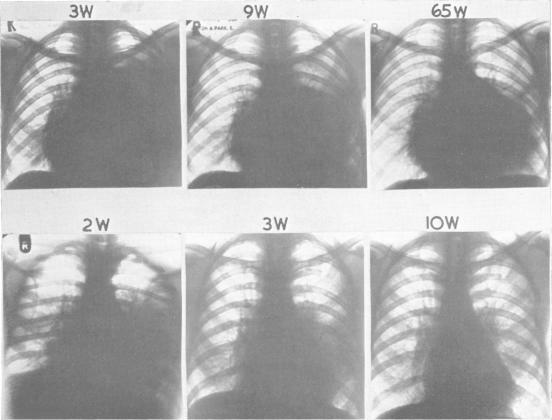

The postcommissurotomy syndrome.

Br Heart J. 1956 Apr;18(2):153-65. doi: 10.1136/hrt.18.2.153.